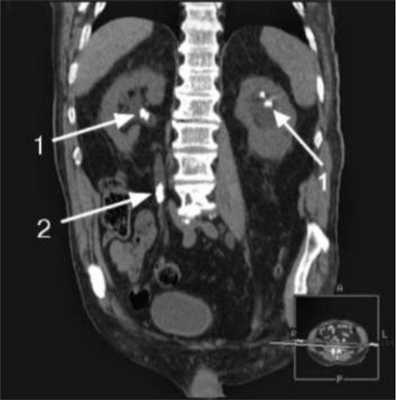

КТ почек без контраста (слева) и с контрастом (справа): стрелками указаны сосуды в воротах почек

Опухоль левой почки, выявленная на КТ мочевыделительной системы с контрастом (указана стрелкой)